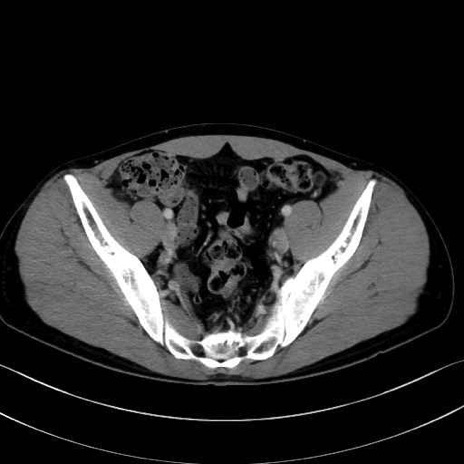

腰方形筋(quadratus lumborum muscle)のCT画像の解剖

2. 腸腰筋群と骨盤底筋

大腰筋 (Psoas major)

腸骨筋 (Iliacus)

肛門挙筋 (Levator ani)

3. 殿部の筋肉(表層・中層・深層)

大殿筋 (Gluteus maximus)

梨状筋 (Piriformis)

内閉鎖筋 (Obturator internus)